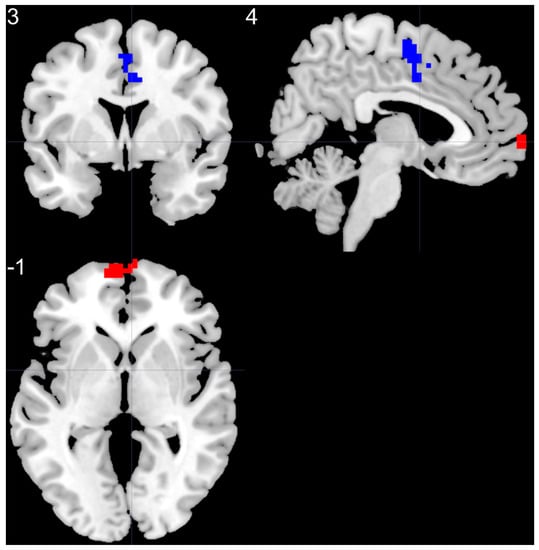

| Brain Regions | Peak T-Scores | MNI Coordinates | Cluster Size (Voxels) | ||

|---|---|---|---|---|---|

| x | y | z | |||

| BD > HC | |||||

| left SMF | 5.37 | −6 | 66 | 0 | 85 |

| BD < HC | |||||

| right SMA | −4.14 | 3 | −6 | 57 | 70 |